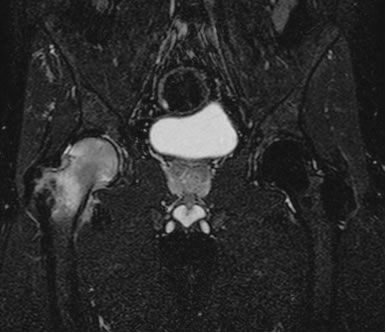

Alla radiografia compare un’area di marcata osteorarefazione a carico della testa del femore (fig.1), la risonanza magnetica evidenzia una diffusa alterazione di segnale a carico dell’epifisi, talora anche della regione trocanterica, espressione dell’edema dell’osso spongioso (fig 2).